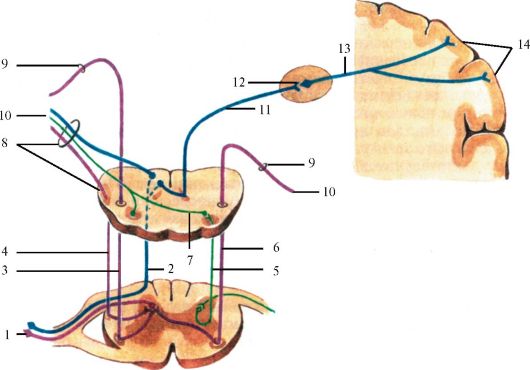

Пирамидная симптоматика в неврологии: ключевые аспекты